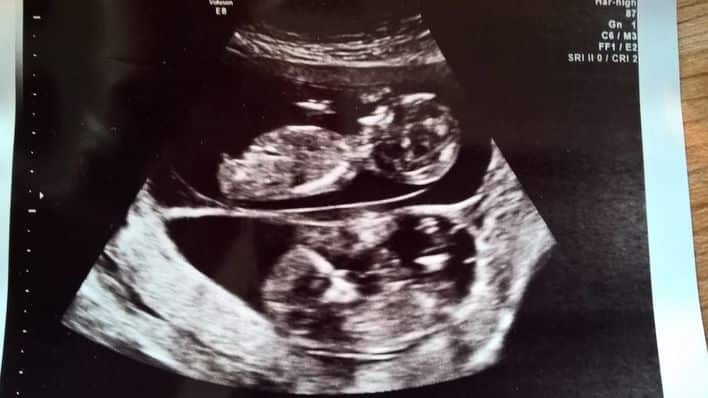

Two Queensland twins have made history after becoming the first pair of semi-identical twins in the world to be identified during pregnancy.

Twins of their kind do not usually survive as embryos, making the now four-year-old siblings just the second set of semi-identical twins in the world.

Deputy Vice Chancellor for Research at the University of New South Wales, Professor Nicholas Fisk made the world-first discovery in 2014.

Now, after going through thousands of other cases of twins around the world, researchers have confirmed the twins were the first of their kind to be identified in pregnancy.